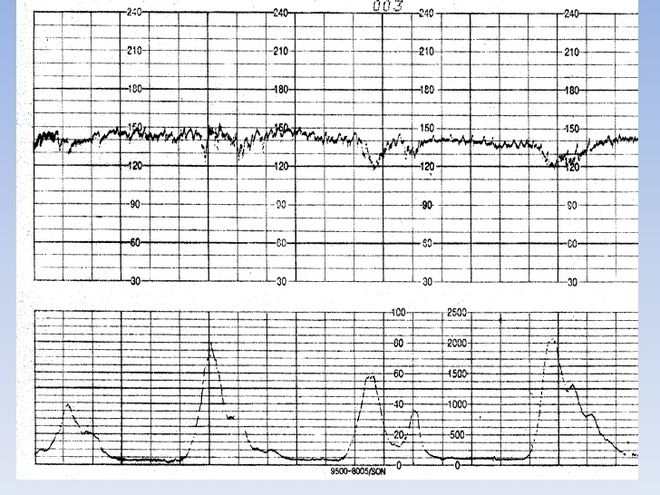

Từ các tuần thai tiếp theo cho đến lúc bé chào đời, tim của thai nhi tiếp tục lớn hơn về kích thước, khối lượng. Bình thường tim thai đập từ 120 – 160 lần /phút.

Vào khoảng tuần thai thứ 12, tim thai của bé gần như đã hoàn thiện. Ở những tuần thai tiếp theo cho đến lúc bé chào đời, tim của thai nhi tiếp tục lớn hơn về kích thước, khối lượng. Bình thường tim thai đập từ 120 – 160 lần /phút, nhưng khi “bé” cựa quậy nhiều thì tim có thể đập nhanh đến 180 lần/phút.

Nhịp tim thai bình thường dao động từ 120 – 160 lần/phút, khi “bé” cựa quậy nhiều thì tim có thể đập nhanh đến 180 lần/phút. Tuy nhiên, nếu vượt quá con số này, mẹ cần phải được thăm khám, theo dõi. Bởi có thể là do mẹ mắc bệnh (bị rối loạn nhịp tim, sốt cao…) hoặc do thai nhi có bệnh lý về tim mạch.

Lưu ý quan trọng là nhịp tim thai chậm gây nguy hiểm cho thai nhi hơn là nhịp thai nhanh, bởi có thể đó là biểu hiện suy thai. Thế nên, khi nhịp tim đập quá chậm chỉ 80 lần/phút, mẹ cần phải biết đó là sự nguy hiểm để được đi cấp cứu ngay.